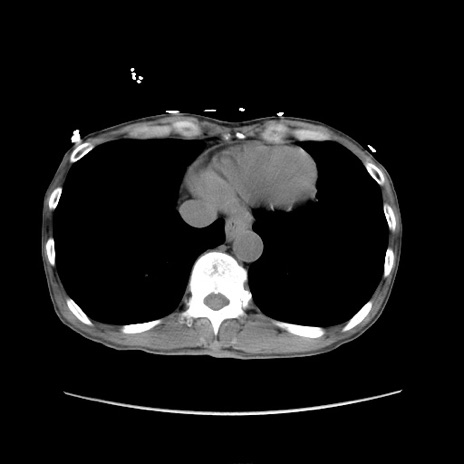

冠状断像